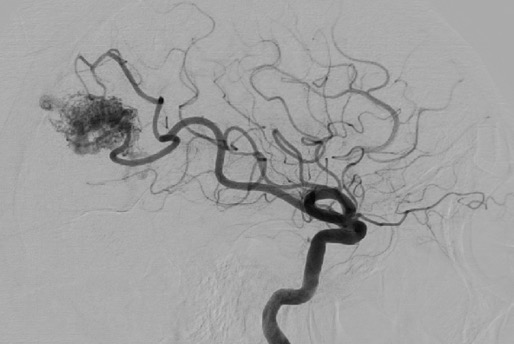

Management of arteriovenous malformations

Our research group has engaged in collaborative efforts within the multi-institutional MISTA registry. Our objective has been to assess the efficacy of stereotactic radiosurgery (SRS), the impact of antiplatelet regimens, the associated risk of hemorrhage, and a comprehensive comparison of various embolization techniques.